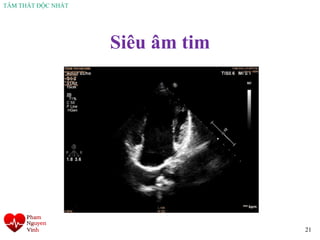

Siêu âm tim

21